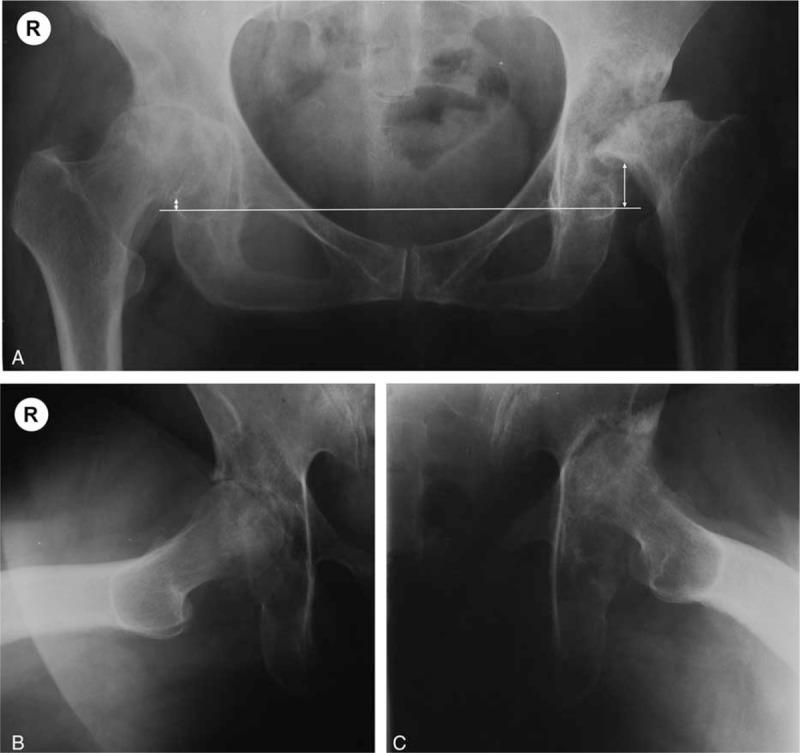

髋关节快速进展性骨关节炎的临床放射学诊断与分级

Due to the current lack of standard definitions for rapidly progressive osteoarthritis of the hip (RPOH) in the literature, this observational study aimed to describe new diagnostic criteria and a grading system for the disease.From a consecutive series of patients undergoing total hip replacement, 2 groups were selected: 1 with RPOH and 1 with primary hip osteoarthritis (POH), and their clinical, paraclinical, and demographic data were compared. The newly proposed clinico-radiological diagnostic criteria are based on characteristics of pain, joint mobility, and radiological assessment. The radiological grading system's inter- and intraobserver reliability was assessed through serial evaluations by 2 blinded reviewers.From the total 863 cases, 82 cases (9.5%) of RPOH were identified and compared with 107 cases of POH. Mean age and disease bilaterality were similar, with a predominance of female patients in the RPOH group (P = 0.03). There were significant differences between the 2 groups in disease onset and aggravation, and intraoperative blood loss. The grading system showed significant inter- and intraobserver agreement (weighted kappa 0.93, and 0.89).Our study presents distinctive, easily recognizable clinico-radiological characteristics of RPOH and confirmed the inter- and intraobserver reliability of the newly proposed grading system.

由于目前文献中缺乏关于髋关节快速进展性骨关节炎(RPOH)的标准定义,本观察性研究旨在描述该疾病的新诊断标准和分级系统。从连续接受全髋关节置换术的患者系列中,选取了2组:1组为RPOH患者,1组为原发性髋关节骨关节炎(POH)患者,并比较了他们的临床、辅助检查和人口统计学数据。新提出的临床放射学诊断标准基于疼痛、关节活动度和放射学评估的特征。通过2名盲法评审员的系列评估,评估了放射学分级系统在观察者间和观察者内的可靠性。在总共863例病例中,确定了82例(9.5%)RPOH患者,并与107例POH患者进行了比较。平均年龄和疾病双侧性相似,RPOH组女性患者居多(P = 0.03)。两组在疾病发作和加重情况以及术中失血量方面存在显著差异。分级系统在观察者间和观察者内显示出显著的一致性(加权kappa分别为0.93和0.89)。我们的研究呈现了RPOH独特的、易于识别的临床放射学特征,并证实了新提出的分级系统在观察者间和观察者内的可靠性。